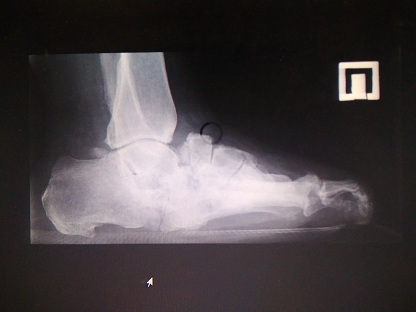

1. Рис.1а | |

| Тема | ||

| Тип | author.submit.suppFile.figureResearchMaterials | |

Посмотреть

(33KB)